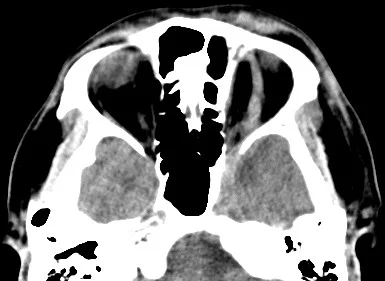

【112-2 醫學(六) 第12題】一位三十餘歲男性主訴視力模糊及眩光,細隙燈檢查可見中間角膜基質之晶狀沉積物及角膜環(arcus)角膜病變(如下圖)。此類病患最可能懷疑血中何物質濃度增高?